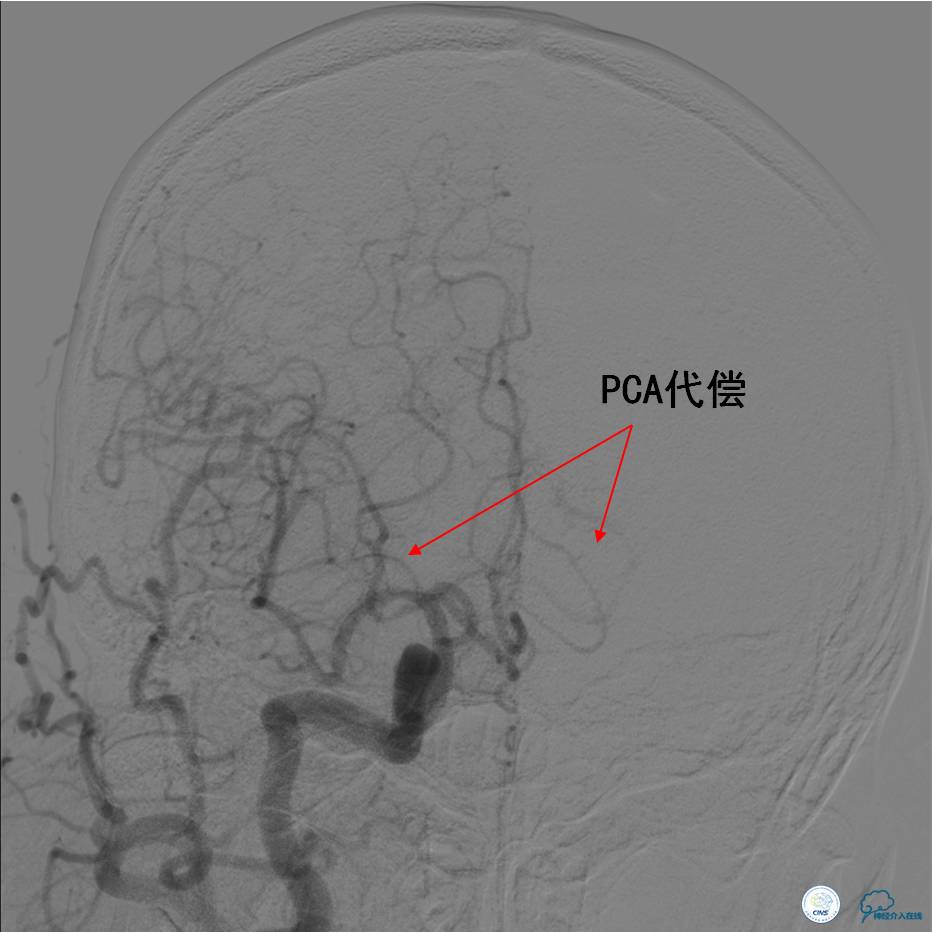

▼DSA:BA重度狭窄、右侧PCA开放。

DSA示TICI分级达到2b级(造影剂完全充盈,包括丘脑的供血,但排空延迟)。